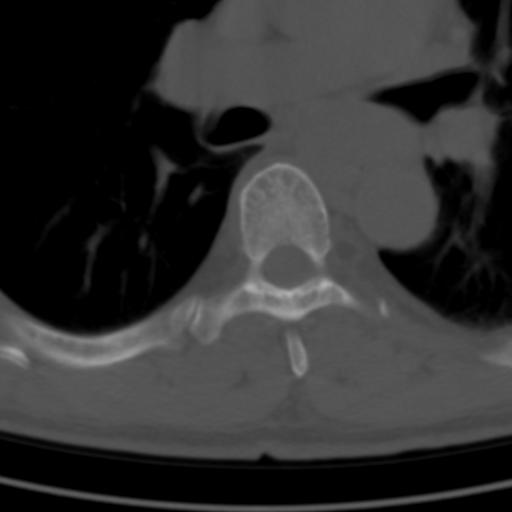

标题: CT25189:胸椎ct,请会诊!

既往食管癌,现行ct检查!

中上段食道癌,椎体轻度退变。

支持中上段食道癌,椎体轻度退变,必要时做ect。